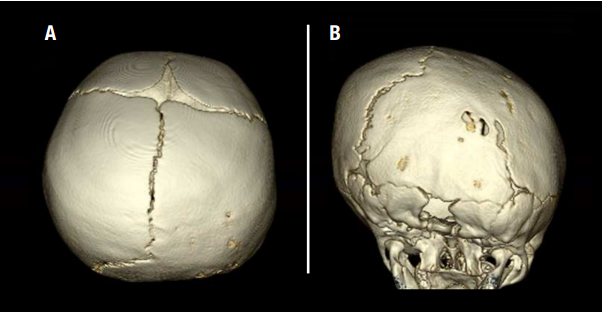

Sometimes, craniosynostosis can be diagnosed with an office examination alone. Often, imaging will be used to more closely examine the cranial sutures and confirm the diagnosis. Here at Nationwide Children’s we use a special CT scan that provides 3D views of the skull using an ultra-low radiation dose equal to that of only a few regular x-rays.